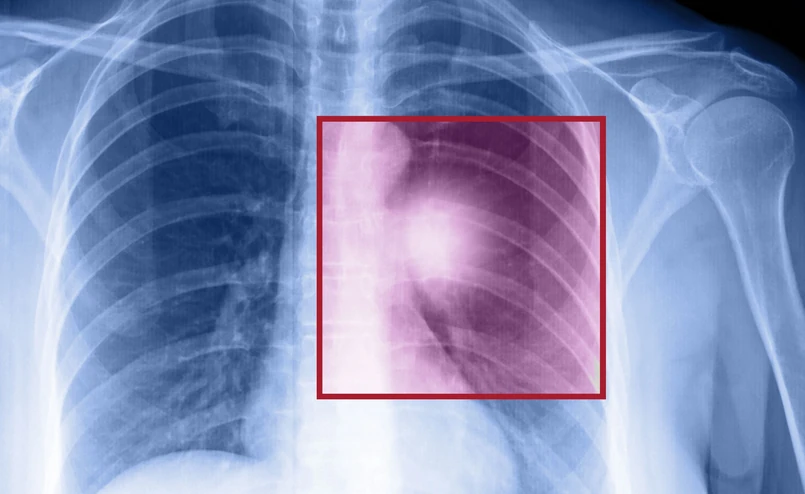

Rak płuc jest pierwszą przyczyna zgonów pacjentów onkologicznych. Według informacji wiceminister Katarzyny Głowali, co roku z tego powodu umiera 16 tys. mężczyzn i 7,5 tys. kobiet. I właśnie w tej grupie chorych obserwuje się wzrost umieralności. W ocenie wiceszefowej resortu zdrowia powodem jest rosnąca liczba kobiet palących papierosy.

Prof. Chorostowska-Wynimko poinformowała, że w Polsce jest bardzo niska pięcioletnia przeżywalność osób chorych na raka. Pięć lat przeżywa 10-15 proc. pacjentów. Profesor podkreśliła, że jedynie leczenie chirurgiczne daje dużą szansę na całkowite wyleczenie. Do tego rodzaju terapii kwalifikuje się jednak zaledwie 20 proc. chorych. Jednym z głównych powodów jest późne diagnozowanie choroby nowotworowej płuc. "Lekarze rodzinni powinni wykazać się wyczuleniem onkologicznym" – powiedziała prof. dr hab. n. med. Halina Batura-Gabryel, krajowy konsultant w dziedzinie chorób płuc. To od nich w dużej mierze zależy prawidłowa diagnoza, a co za tym idzie - szybkie wdrożenie terapii.